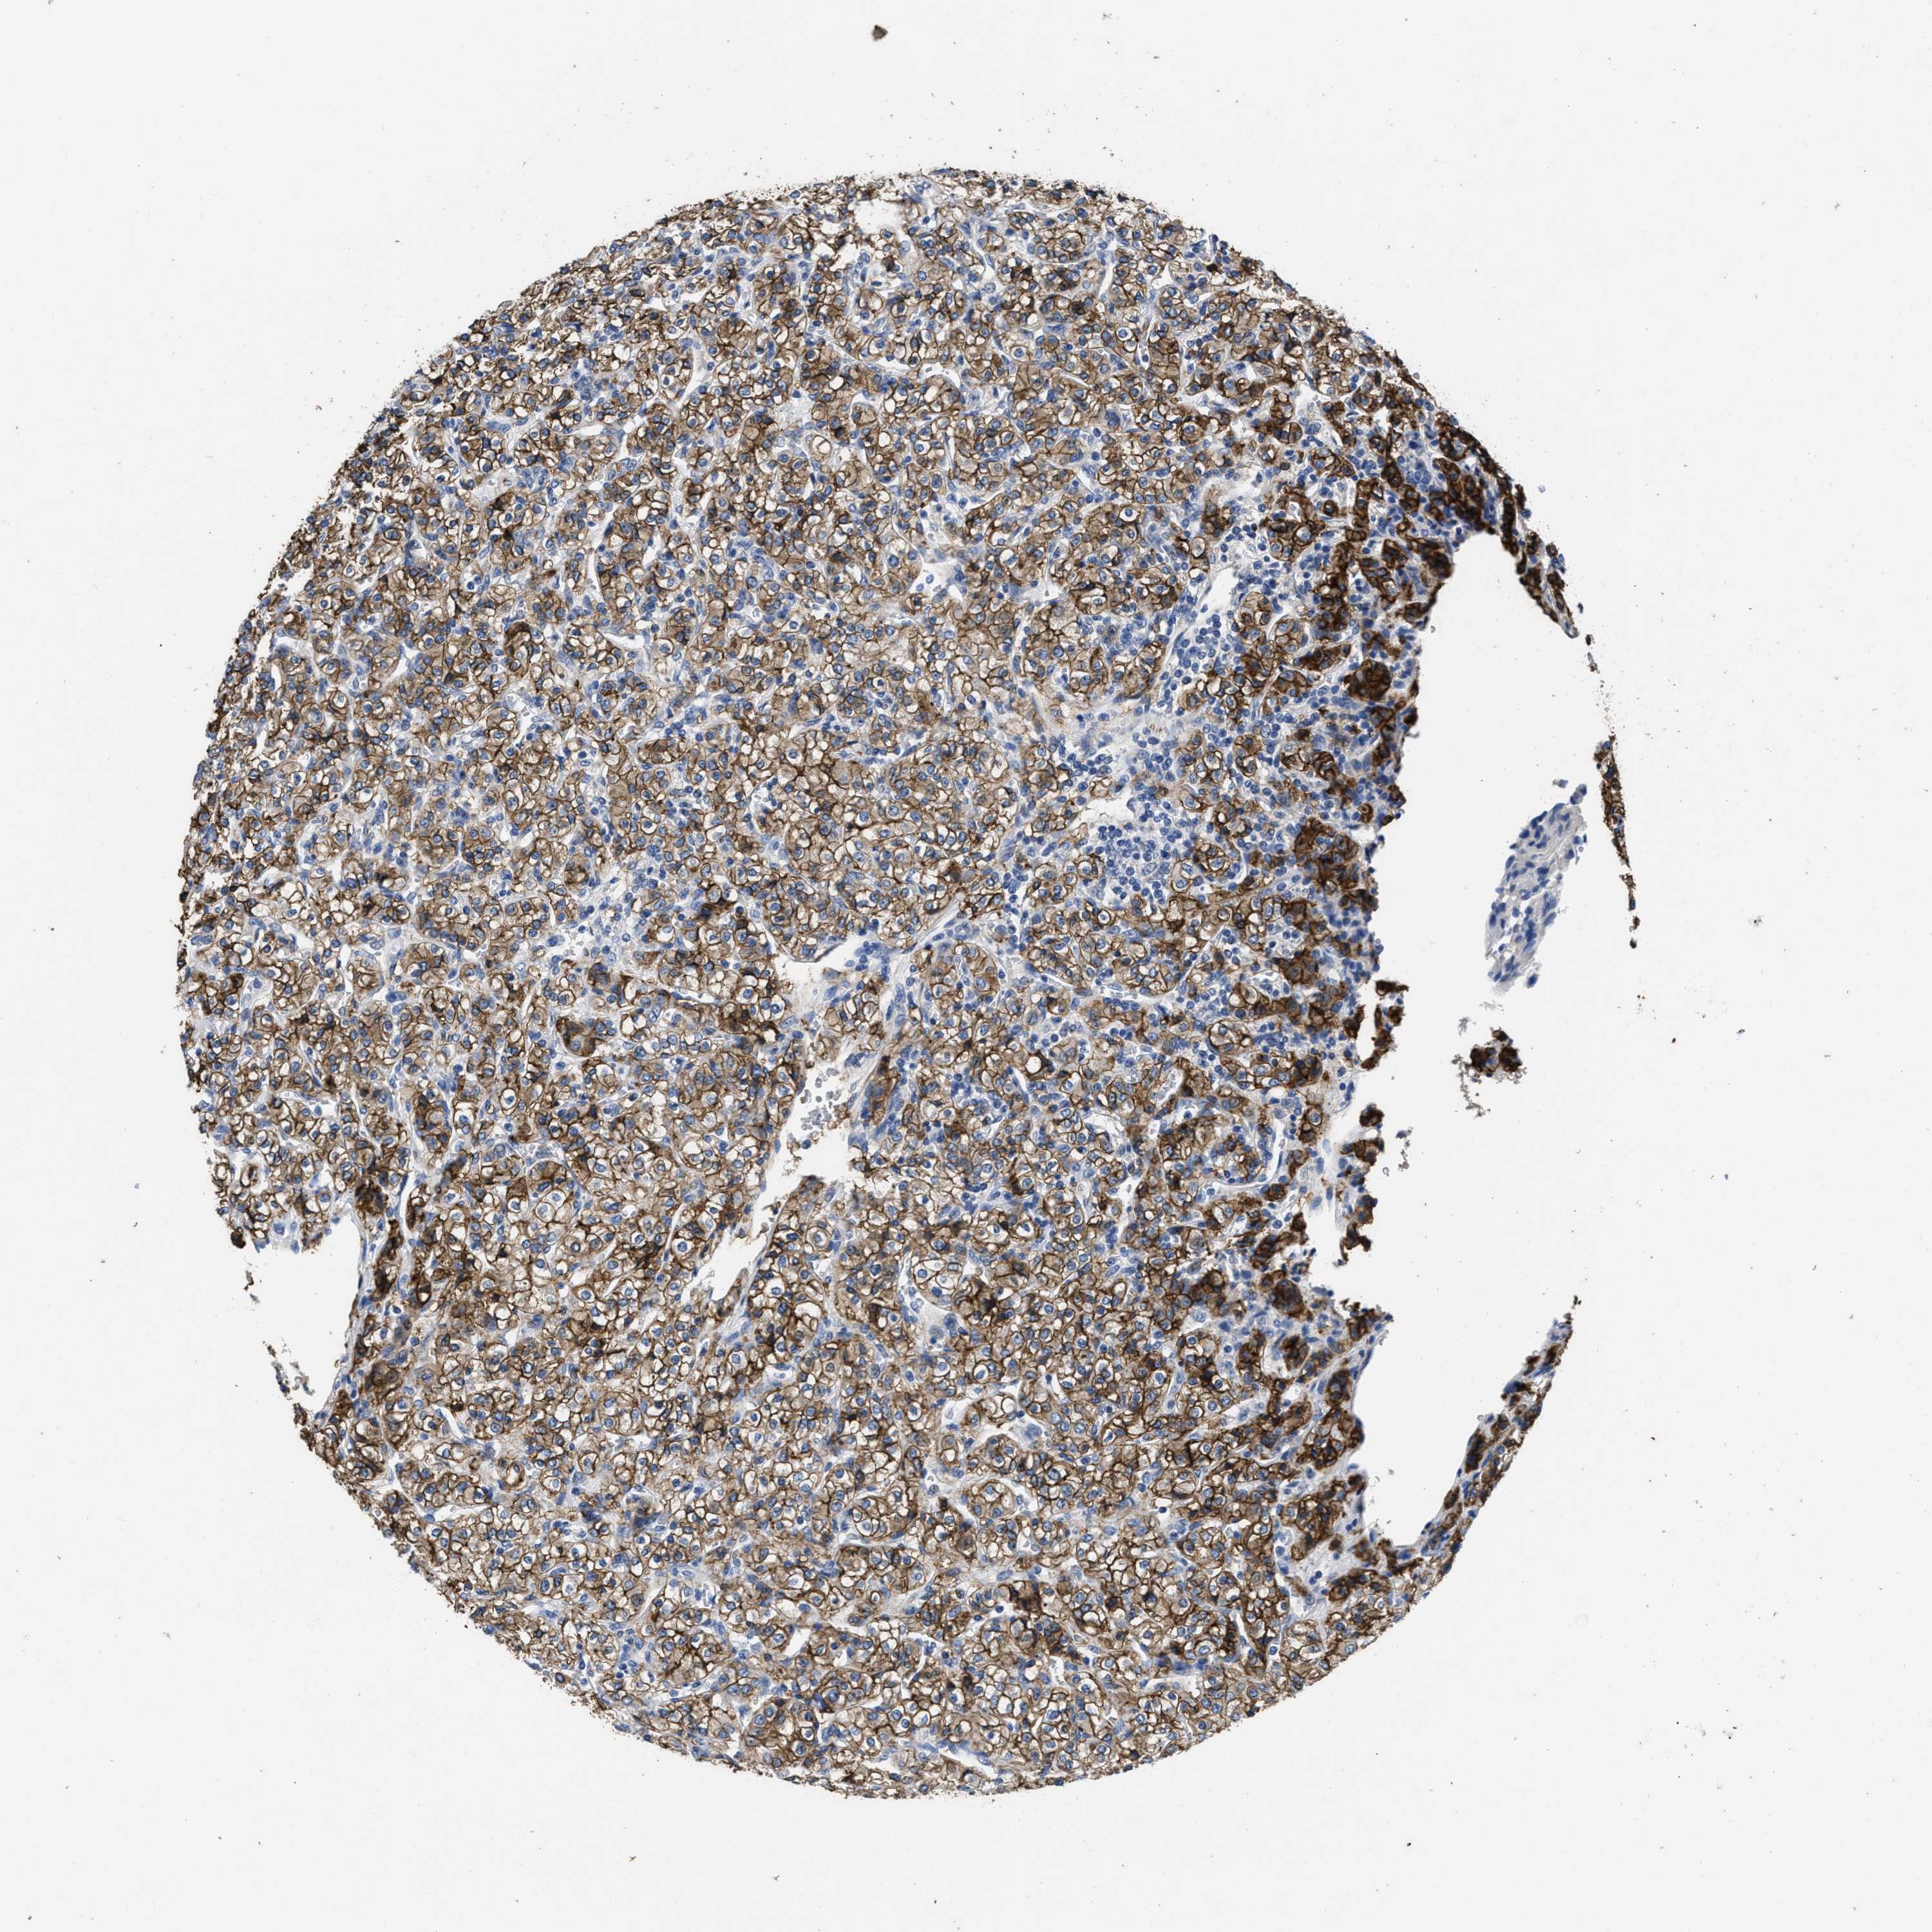

CANCER RENAL CANCER Show tissue menu

KIDNEY RENAL CLEAR CELL CARCINOMA (TCGA) - Interactive survival scatter ploti

& Survival analysisi

Kaplan-Meier plots summarize results from analysis of correlation between mRNA expression level and patient survival. Patients were divided based on level of expression into one of the two groups "low" (under cut off) or "high" (over cut off). X-axis shows time for survival (years) and y-axis shows the probability of survival, where 1.0 corresponds to 100 percent.

CA9 is potential prognostic, high expression is favorable in Kidney Renal Clear Cell Carcinoma (TCGA)

TCGA RNA samplesi

RNA-seq data is reported as average FPKM (number Fragments Per Kilobase of exon per Million reads), generated by the The Cancer Genome Atlas (TCGA) .

Normal distribution across the dataset is visualized with box plots, shown as median and 25th and 75th percentiles. Points are displayed as outliers if they are above or below 1.5 times the interquartile range. FPKM values of the individual samples are presented next to the box plot.

Average pTPM 219.1

Number of samples 521